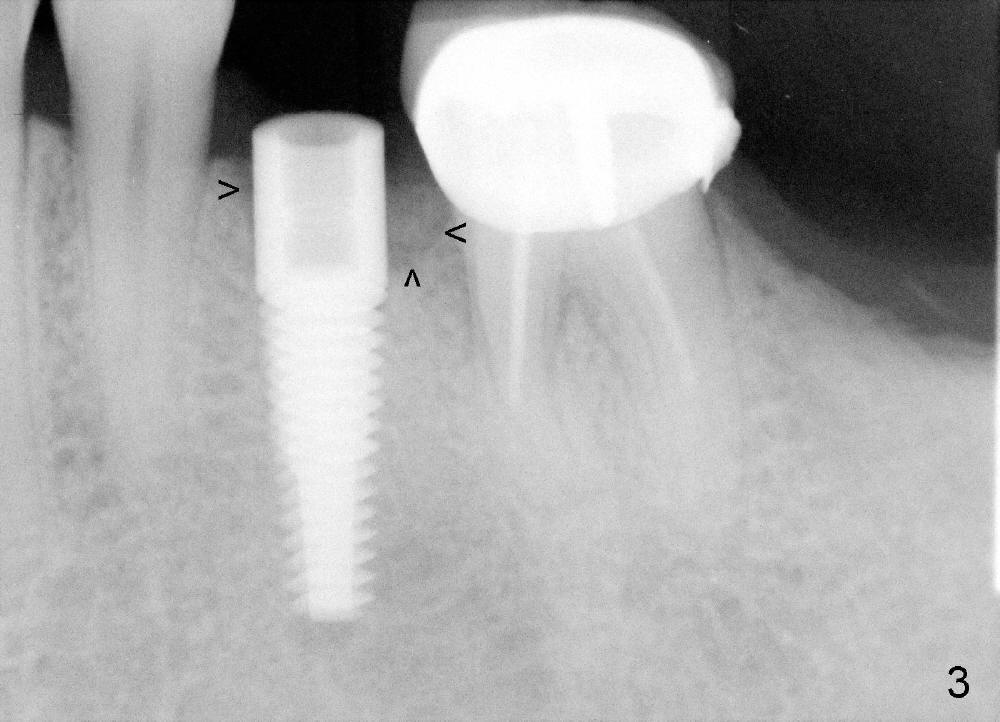

A 44-year-old lady has poor dentition. The tooth #20 has a residual root (Fig.1 R). Immediately after extraction, osteotomy is formed by drills (Fig.2: 3.5x17 mm); a 4.5x17 mm implant is placed (Fig.3 (arrowheads: boundary of the socket)). The patient returns 9 months later with increased radiolucency around the implant (Fig.4) and buccal swelling (Fig.5, asymptomatic). Raising the buccal flap confirms bone loss around the implant (Fig.6). Following debridement, allograft is placed. The source of the infection is unknown.